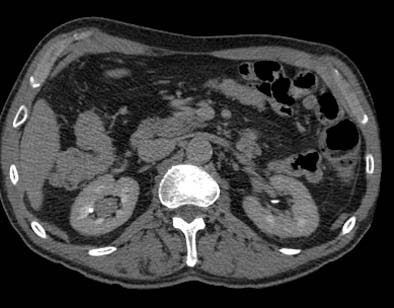

| Postprocessing or reformatting images may obscure the diagnosis. TCC clearly seen on axial CT (above) and on coronal multiplanar reformat below. But even a thin-slab MIP reformat masks detection of the right-upper-pole TCC (bottom). Images courtesy of Dr. Nigel Cowan. |